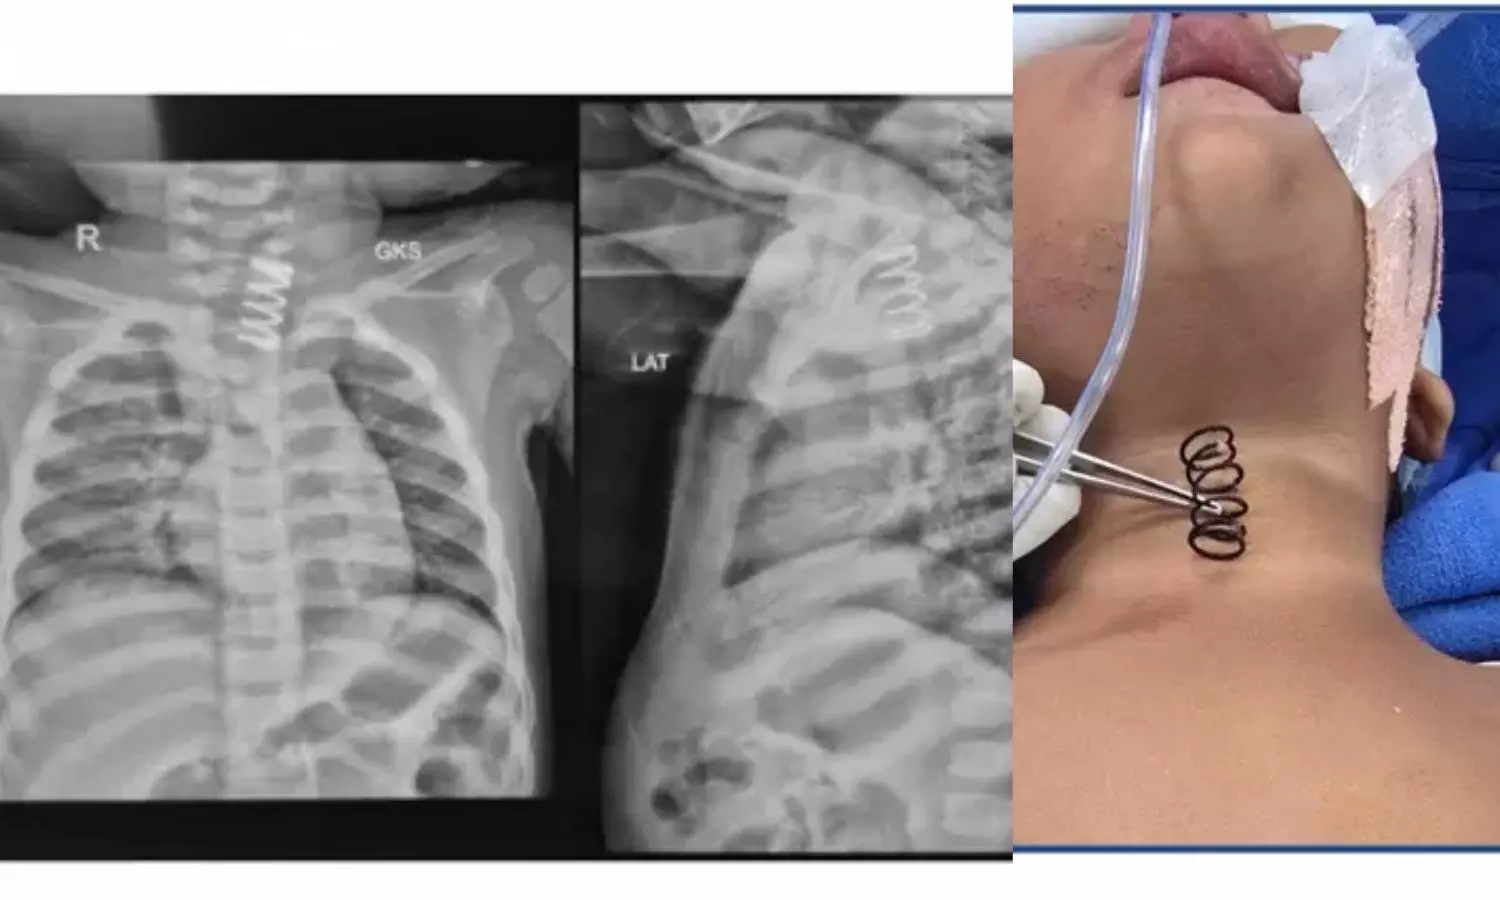

जांच के दौरान एक्स-रे में साफ़ दिखा कि बच्ची की खाद्य नली में एक बड़ा धातु का स्प्रिंग फंसा हुआ है। इसके आसपास नली की अंदरूनी परत में घाव और सूजन भी देखी गई, जिससे स्थिति और ज्यादा गंभीर हो गई थी।

पेडियाट्रिक सर्जरी विभाग के प्रोफेसर डॉ. विशाल जैन ने बताया कि यह स्प्रिंग सामान्य पेन के स्प्रिंग से कहीं ज्यादा मोटा था। इसकी चौड़ाई लगभग आधा इंच और लंबाई करीब 1.5 से 2 इंच थी, जिससे इसे निकालना बेहद चुनौतीपूर्ण था। इससे पहले देहरादून के एक निजी अस्पताल में इसे निकालने की कोशिश की गई थी, लेकिन सूजन और घाव के कारण वहां सर्जरी करना जोखिम भरा माना गया। इसके बाद बच्ची को तुरंत एम्स रेफर किया गया।

एम्स में डॉक्टरों की टीम ने ऑपरेशन थिएटर में उन्नत एंडोस्कोपिक तकनीक का इस्तेमाल किया। स्प्रिंग को बहुत सावधानी से घुमाते हुए बाहर निकाला गया, ताकि खाद्य नली में किसी तरह का छेद या गंभीर चोट न पहुंचे। सर्जरी पूरी तरह सफल रही।